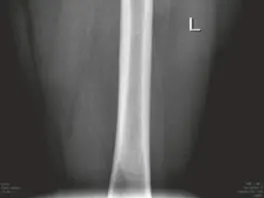

• الأشعة السينية العادية (Plain Radiographs):

• تُعد الأشعة السينية هي الخطوة الأولى والأكثر أهمية في تقييم الاحتكاك الفخذي الحقي. يتم أخذ عدة لقطات من زوايا مختلفة:

• النظر الأمامي الخلفي للحوض (AP Pelvis): ل